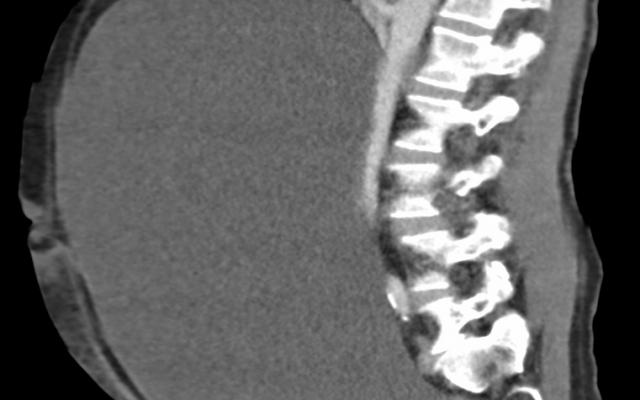

Een 61-jarige man met een verstandelijke beperking kwam op de SEH met een pijnlijke, bolle buik. Hij had sinds een week geen ontlasting meer gehad; hij was niet misselijk en had niet gebraakt. Patiënt werd al enkele dagen behandeld met laxantia en meerdere klysma’s, zonder resultaat.

Wij zagen een niet acuut zieke man. Behoudens een tachycardie waren de controles niet afwijkend. Bij lichamelijk…